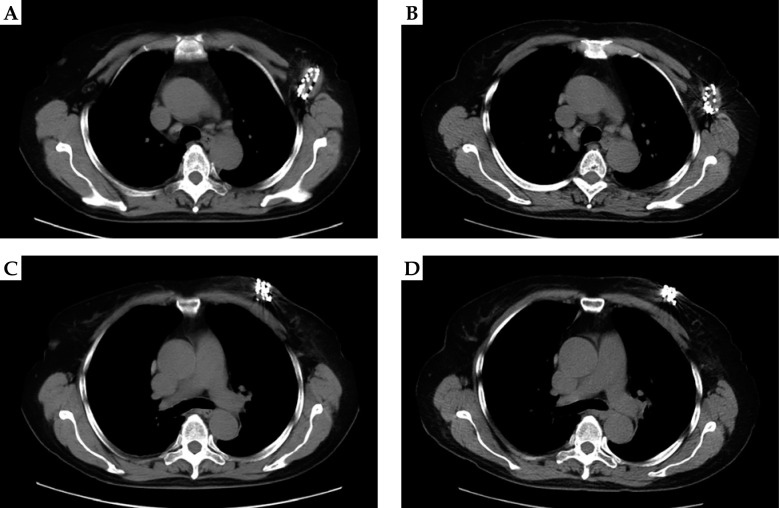

Material and methods: A retrospective analysis was conducted on the clinical data of 68 patients with unresectable locoregionally recurrent breast cancer who underwent radioactive 125I seed implantation therapy at our hospital between January 2018 and October 2023. All patients received CT-guided 125I seed implantation. Postoperatively, follow-up was carried out to calculate the local control rate, monitor the occurrence of complications, and compare the serum levels of carcinoembryonic antigen (CEA) and carbohydrate antigen 153 (CA153) before and after treatment.

Results: A total of 89 locally recurrent lesions were identified in the 68 patients. The 125I seed implantation procedure achieved a success rate of 97.75% (87/89), with a local control rate (LCR) of 88.76% (79/89) and an objective response rate (ORR) of 75.28% (67/89). Stratified by initial clinical stage, the ORR was 80.00% (20/25) in patients with stage I + II disease and 67.44% (29/43) in those with stage III + IV disease, showing a statistically significant difference (χ2 = 9.822, p < 0.001). The pain relief effective rate at 1 month postoperatively was 91.18%. For the 68 patients, the median local progression-free survival (LPFS) was 25.60 months (95% confidence interval [CI]: 20.36-26.70), with 1-year, 2-year, and 3-year LPFS rates of 82.35%, 52.94%, and 17.65%, respectively. The median overall survival (OS) was 36.65 months (95% CI: 34.50-40.20), with 1-year, 2-year, and 3-year OS rates of 95.59%, 70.59%, and 51.47%, respectively. Univariate and multivariate analyses identified primary tumor stage, molecular subtype, treatment modality, and recurrence site as key factors influencing survival in locally recurrent breast cancer, with respective hazard ratios (HR) of 2.473 (p = 0.042), 1.359 (p = 0.036), 1.166 (p = 0.011), and 1.997 (p = 0.014). The median LPFS was 28.60 months in patients with initial clinical stage I + II and 20.36 months in those with stage III + IV, with a statistically significant difference (χ2 = 4.567, p = 0.0326). The median LPFS was 25.95, 25.60, 20.36, and 11.55 months for patients with Luminal A, Luminal B, HER-2-positive, and triple-negative subtypes, respectively, with a statistically significant difference (χ2 = 4.068, p = 0.0437). The median LPFS was 25.60 months in the 60 patients who received systemic therapy vs. 13.55 months in the 8 patients who received monotherapy alone, with a statistically significant difference (χ2 = 9.170, p = 0.0025). For patients with multi-site recurrence (n = 15) and single-site recurrence (n = 53), the median LPFS was 15.60 months and 25.60 months, respectively, with a statistically significant difference (χ2 = 4.060, p = 0.0439). Following 125I seed implantation, most adverse reactions were grade 1 or 2, with an overall incidence of 36.96%, and no severe postoperative complications were observed.

Conclusions: CT-guided 125I seed brachytherapy for locoregionally recurrent breast cancer is characterized by definite efficacy, minimal invasiveness, and fewer complications compared with external beam radiotherapy. It can serve as an important treatment option for locoregionally recurrent breast cancer, particularly in cases with poor control of localized progression-free survival, such as advanced disease, multisite recurrences, and triple-negative breast cancer, which is prone to distant metastasis.